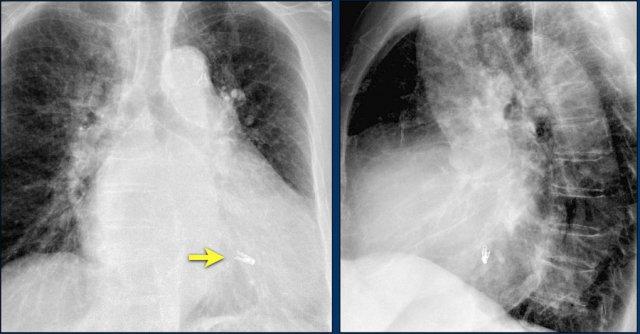

Hình ảnh X-quang ngực cho thấy vị trí đặt Impella đúng kỹ thuật với đầu vào (mũi tên vàng) và đầu ra (mũi tên trắng) lần lượt nằm ở tâm thất trái và động mạch chủ lên.